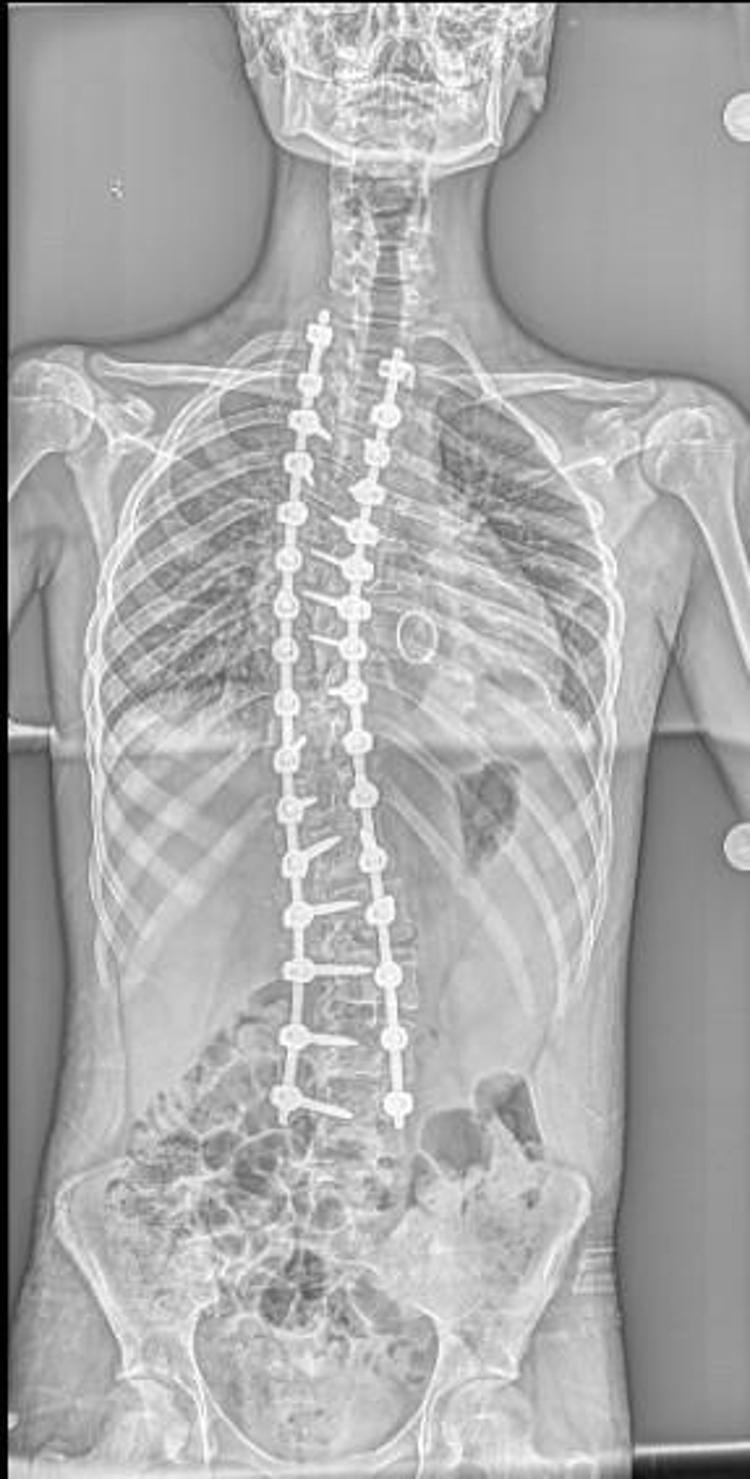

Eren'in sırt bölgesinde 90, bel bölgesinde 70 dereceye ulaşan eğrilik tespit edildi. Eren, kalp kapağı ameliyatı nedeniyle kullandığı kan sulandırıcı ilaçlar kesilmeden biri 8 saat, diğeri 6 saat olmak üzere 2 seanslık riskli operasyonla skolyozdan kurtuldu. Eren, yüksek miktarda kan kaybı yaşamasına rağmen başarılı geçen operasyonun ardından sağlığına kavuştu.

İlk ameliyatında ciddi kanaması olmasından dolayı ilk ameliyatını birinci seans olarak tamamlayamadan bitirmek zorunda kaldık. İmplantlarını yerleştirip, ameliyatı sonlandırdık. Genel durumu toparladıktan sonra birkaç hafta geçip, değerleri de normal değerlere geldikten sonra ikinci seans olarak tekrar ameliyata aldık. İkinci seansta omurgadaki düzeltme işlemlerini tamamlayıp operasyonumuzu bitirdik" diye konuştu.

Ama Eren’de bunu yapamadık. Bu da Eren’in ilk ameliyatta kan kaybını artırdı. İlk ameliyatta ciddi kan kaybı yaşadık, operasyonu yarıda bırakmak zorunda kaldık. Kan tablosu normal değerlere geldikten sonra ikinci seans ameliyata aldık. Onun için daha güvenli olacak şekilde iki aşamada ameliyatını tamamladık. Şu an durumu iyi. Fizik tedaviye başlayacak ve kademeli olarak normal hayatına dönecek" dedi.